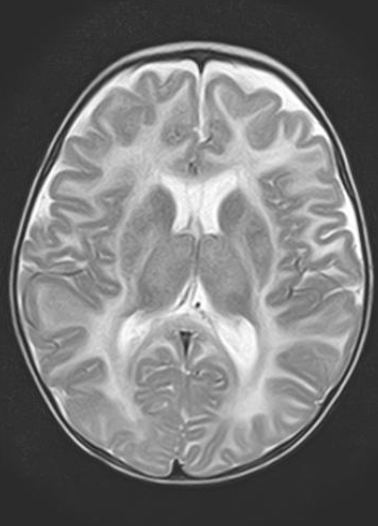

Imagem 3

A intoxicação por monóxido de carbono (CO)